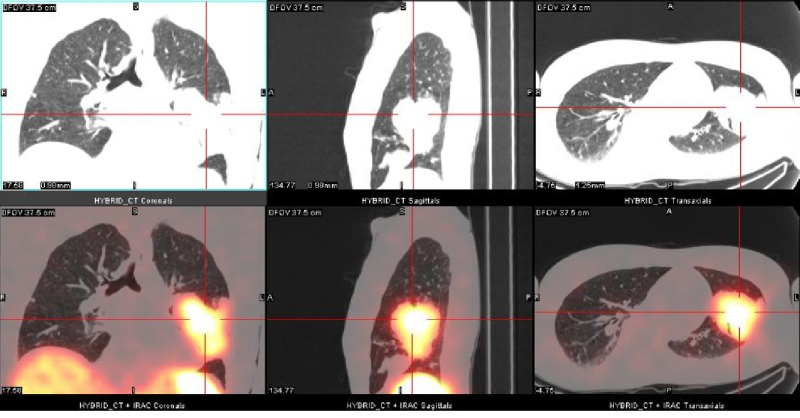

Uma quarta recorrência foi identificada por RM na região retro-orbital direita com progressão ipsilateral anterior para lobo temporal após cinco anos. Investigação pré-operatória constatou uma massa pulmonar na parte inferior do lobo superior esquerdo. Biópsia guiada por CT evidenciou meningioma atípico grau II. Um estudo com 111In-Oct SPECT/CT foi realizado como extensão diagnóstica. Foi evidenciada intensa fixação do 111In-Oct associada à presença de receptores de somatostatina a nível da lesão pulmonar (fig. 1), assim como na lesão temporal direita (fig. 2), confirmando recorrência. Tambén foi detectada fixação linfonodal direita (fig. 3).